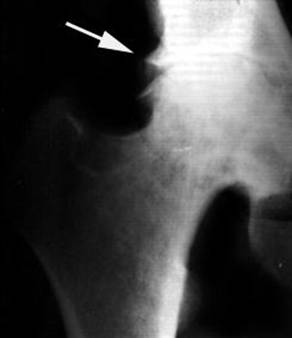

Ранним рентгенологическим симптомом являются краевые костные разрастания — остеофиты — следствие активной пролиферации периферических отделов суставного хряща. Они проявляются вначале заострением краев суставных поверхностей, а затем, нарастая, образуют массивные костные шипы и губы. Краевые остеофиты, как правило, раньше обнаруживаются со стороны суставных впадин.

Сужение суставной щели свидетельствует о значительных изменениях суставных хрящей. Суставная щель может стать клиновидной, суживаясь с одной стороны и нередко расширяясь при этом с противоположной, что указывает на недостаточность связочного аппарата и нестабильность сустава.

При остеоартрозе утрачивается амортизационная функция суставных хрящей, предохраняющих костную ткань от механических перегрузок. Как компенсация развивается остеосклероз субхондральной губчатой кости. Особенно он выражен при коксартрозе в крыше вертлужной впадины, распространяясь иногда почти на все тело подвздошной кости. Однако рано или поздно этот механизм компенсации становится недостаточным. Механические силы, передающиеся непосредственно с одной суставной поверхности на другую, вызывают атрофию от давления их наиболее нагружаемых участков и прежде всего центральных отделов суставных головок. Вследствие этого они уплощаются и одновременно расширяются.